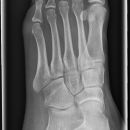

Fuß a.p.

Komplexe anatomische Verhältnisse => Zusätzlich Schräg- und evtl. noch streng-seitliche Aufnahmen oder Vergleichsaufnahmen der Gegenseite anfertigen! Komplexe Luxationen/ Frakturen => großzügige CT-Indikation! Zentrale Kalkaneusfrakturen (vgl. Kalkaneus) => absolute CT-Indikation! Isolierte Frakturen des Os naviculare, der Ossa cuneiforma oder des Cuboids sind Raritäten => Immer nach zusätzlichen Verletzungen (Calcaneus, Talus, OSG,...) suchen!

Beurteilungskriterien

- Korrekte Stellung der Fußwurzelknochen zueinander? Kongruente Gelenkflächen? Gelenkspaltweiten zwischen den Fußwurzelknochen und Tarsometatarsalgelenken < 2,5mm? Interphalangealgelenke < 2mm? Luxation? Luxationen meist mit Frakturen (v.a. Talushals, Kalkaneus, OSG-Frakturen, Metatarsalbasen) kombiniert!

- "target areas" subtiler Frakturen: Talushals, Proc.ant.calcanei, Sustentaculum, Tuberositas ossis metatarsalis V!!!

- Typische Lokalisationen von Kapsel-Band-Ausrissen am Metatarsus:

- Os naviculare: dorsomedialer Sehnenausriss (Avulsion der Tuberositas, Ansatz M.tibialis post.)=> seitl. Aufnahme (DD Os supranaviculare)

- Os cuboideum: ventroplantarer, knöcherner Ausriss (M.tibialis post.)

- Tuberositas ossis metatarsalis V (M.peronaeus brevis) <=> DD Os peronaeum, Os Vesalianum

Cave:

- akzessorische Knochen (abgerundet mit zirkulärer Kortikalis, z.B. Os supranaviculare, Os supratalare, Os tibiale externum, Os Vesalianum, Os peroneum, Calcaneus secundarius, Os intercuneiforme) und Normvarianten der Apophsenentwicklung im Wachstumsalter, z.B. mehrkernige Tuberapophyse am Achillessehnenansatz, persistierender Apophysenkern der Basis ossis metatarsalis V.

- Ermüdungsfrakturen initial oft nicht erkennbar => Röntgenkontrolle in 8-10d.